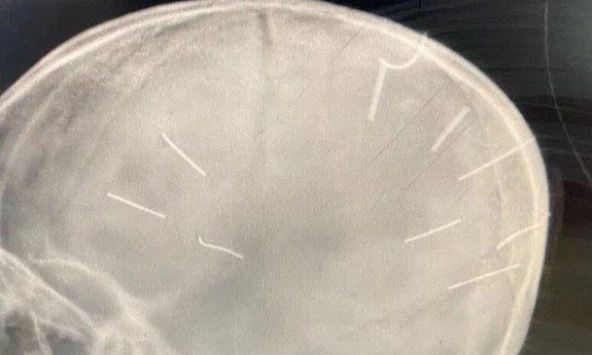

![]() |

| Dị vật là phần cuống trái xoài |